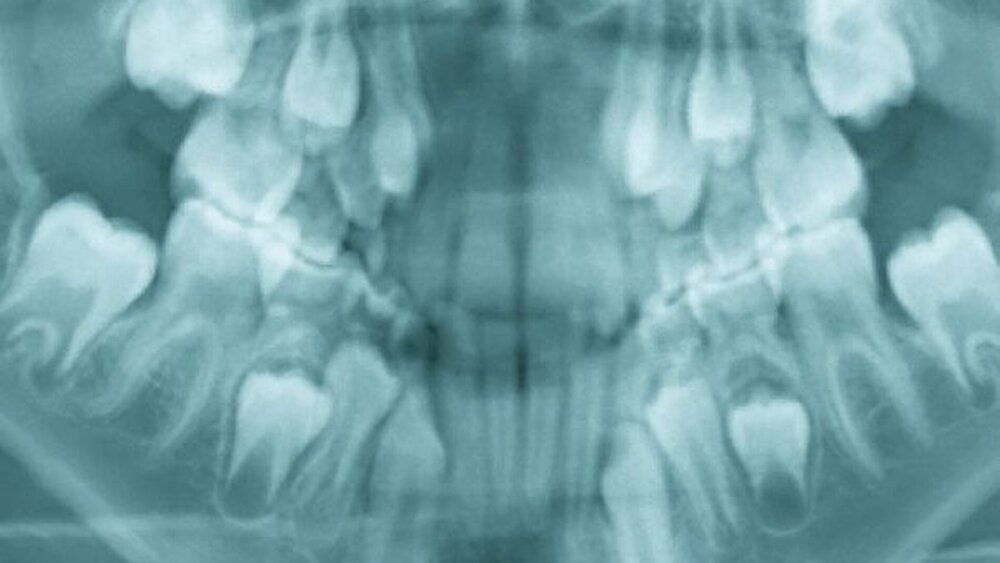

Klinisch und radiologisch (Abbildung 1a bis b) zeigte sich eine deutliche Intrusion des linken oberen zentralen Schneidezahns, verursacht durch einen Sturz während des Spielens. Weitere Verletzungen konnten ausgeschlossen werden.

Das kieferorthopädische Behandlungskonzept sah die orthodontische Extrusion (Reposition) und Wiedereinstellung des zentral luxierten Zahnes 21 vor. Dazu wurde ein Bracket auf den traumatisierten Zahn geklebt. Über eine zunächst punktförmige Anbindung eines Extrusionsbogens und geringer orthodontischer Kräfte wurde der Zahn schrittweise eingestellt (Abbildung 2a). Um während der Einstellung des intrudierten Zahnes unerwünschte Nebenwirkungen (sagittal, transversal und vertikal) im posterioren Bereich der Molaren zu vermeiden, wurde zusätzlich ein Transpalatinalbogen als Verankerungsverstärkung (Abbildung 2b) verwendet. Abbildung 3a bis b zeigt den klinischen und röntgenologischen Endbefund.